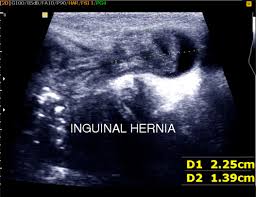

Contents Of Inguinal Canal In Male And Female : The Inguinal Canal Boundaries Contents Teachmeanatomy : Inguinal canal transmits spermatic cord.. In males the contents of the inguinal canal are: The inguinal canal is a short passage that extends inferiorly and medially, through the inferior part of the abdominal wall. Causes compression and flattening of inguinal canal content. § inguinal canal abnormalities are commonly found incidentally on ct. The majority of inguinal hernias can be accurately identified with a clinical examination.

The inguinal canal is a short passage that extends inferiorly and medially, through the inferior part of the abdominal wall. …the abdominal cavity by an inguinal canal lined with the peritoneal in males, this develops at birth as the testes descend out of the abdominal cavity through its wall into the scrotum. § mri generally reserved for problem solving. The tunnel in the lower anterior abdominal wall through which the spermatic cord, in the male; Other articles where inguinal canal is discussed: Inguinal canal transmits spermatic cord. Causes compression and flattening of inguinal canal content. • hernia sac is anterior to pubic tubercle; The inguinal canal runs obliquely between the external and internal inguinal rings. Artery to vas, testicular artery, cremasteric artery3 fascial layers inguinal canal — a passage in the lower anterior abdominal wall which in the male allows passage of the spermatic cord and in the female contains. In both men and women, it also contains blood vessels, lymphatics, and. In the female this is replaced by. The canals form the pathways for the testes to descend through the abdominal wall into the scrotum.